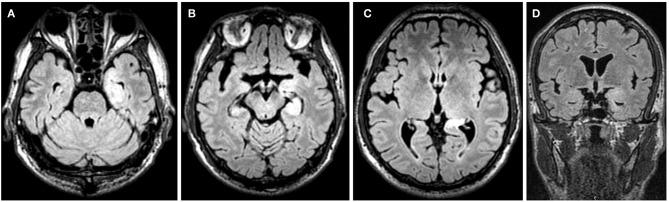

To investigate clinical and electroencephalographic features of the seizures in different types of neuronal surface antibody (NSAb)-associated autoimmune encephalitis (AE). The clinical data of the seizures were analyzed in 18 patients with NSAb-associated AEs diagnosed in the First Affiliated Hospital of Dalian Medical University. From May 2013 to April 2019, a total of 18 cases of NSAb-associated AE were diagnosed, including 9 cases of leucine-rich glioma-inactivated 1 protein (LGI1) antibody-associated encephalitis, 7 cases of anti--methyl-d-aspartate receptor (NMDAR) encephalitis, and 2 cases of anti-γ-aminobutyric acid B receptor (GABAR) encephalitis. All nine cases (100%) with LGI1 AE had seizures manifesting in three types: faciobranchial dystonia seizure (FBDS) (44.4%), mesial temporal lobe epilepsy (MTLE)-like seizure (66.7%), and focal to bilateral tonic-clonic seizure (FBTCS) (77.8%). Six of nine (66.7%) showed abnormal signal on hippocampus or basal ganglia in brain MRI. Five of seven cases (71%) with anti-NMDAR encephalitis had seizures manifesting in three types: focal aware seizure (40%), focal-impaired awareness seizure (20%), generalized tonic-clonic seizure (GTCS) (100%), and status epilepticus (SE) (40%). Three of seven (42.8%) showed abnormalities in brain MRI. Both patients with anti-GABAR encephalitis had seizures manifesting in two types: GTCS and MTLE-like seizure, one with SE. One showed abnormal signal on left hippocampus in brain MRI. All patients (100%) with three types of AE had abnormalities in electroencephalogram (EEG), showing diffuse (4/18) or focal slow waves (14/18) in background, interictal (10/18), or ictal (6/18) epileptic discharges in the temporal or other regions; two patients with anti-NMDAR encephalitis showed delta activity or rhythm in frontotemporal region. All patients with seizures showed good response to immunotherapy except one with LGI1 AE. Most patients with NSAb-associated AE had seizures; seizure types varied between different types of AE. In LGI1 AE, the hippocampus and basal ganglia were two main targets; the corresponding seizure type was MTLE-like seizure and FBDS, respectively. Anti-NMDAR encephalitis had more generalized than focal seizures. Delta activity or rhythm in the frontotemporal region in EEG was helpful for diagnosis. Anti-GABAR encephalitis was characterized by refractory seizures as initial symptom, mainly GTCS or MTLE-like seizure. Most seizures in NSAb-associated AE showed good response to immunotherapy, and antiepileptic drugs should be considered as an add-on symptomatic treatment.

探讨不同类型神经元表面抗体(NSAb)相关自身免疫性脑炎(AE)发作的临床及脑电图特征。分析大连医科大学附属第一医院确诊的18例NSAb相关AE患者发作的临床资料。2013年5月至2019年4月,共确诊18例NSAb相关AE,其中9例为富含亮氨酸胶质瘤失活1蛋白(LGI1)抗体相关脑炎,7例为抗N-甲基-D-天冬氨酸受体(NMDAR)脑炎,2例为抗γ-氨基丁酸B受体(GABAR)脑炎。所有9例LGI1 AE患者(100%)均有发作,表现为三种类型:面臂肌张力障碍发作(FBDS)(44.4%)、内侧颞叶癫痫(MTLE)样发作(66.7%)和局灶性至双侧强直阵挛发作(FBTCS)(77.8%)。9例中有6例(66.7%)脑MRI显示海马或基底节信号异常。7例抗NMDAR脑炎患者中有5例(71%)发作表现为三种类型:局灶性意识发作(40%)、局灶性意识障碍发作(20%)、全面强直阵挛发作(GTCS)(100%)和癫痫持续状态(SE)(40%)。7例中有3例(42.8%)脑MRI显示异常。2例抗GABAR脑炎患者发作均表现为两种类型:GTCS和MTLE样发作,1例伴有SE。1例脑MRI显示左侧海马信号异常。三种类型AE的所有患者(100%)脑电图(EEG)均有异常,表现为背景弥漫性(4/18)或局灶性慢波(14/18),发作间期(10/18)或发作期(6/18)颞叶或其他区域癫痫样放电;2例抗NMDAR脑炎患者额颞区出现δ活动或节律。所有发作患者除1例LGI1 AE患者外,对免疫治疗反应良好。大多数NSAb相关AE患者有发作;不同类型AE的发作类型不同。在LGI1 AE中,海马和基底节是两个主要靶点;相应的发作类型分别为MTLE样发作和FBDS。抗NMDAR脑炎全身性发作多于局灶性发作。EEG额颞区的δ活动或节律有助于诊断。抗GABAR脑炎以难治性发作作为初始症状为特征,主要为GTCS或MTLE样发作。NSAb相关AE的大多数发作对免疫治疗反应良好,抗癫痫药物应作为附加的对症治疗。